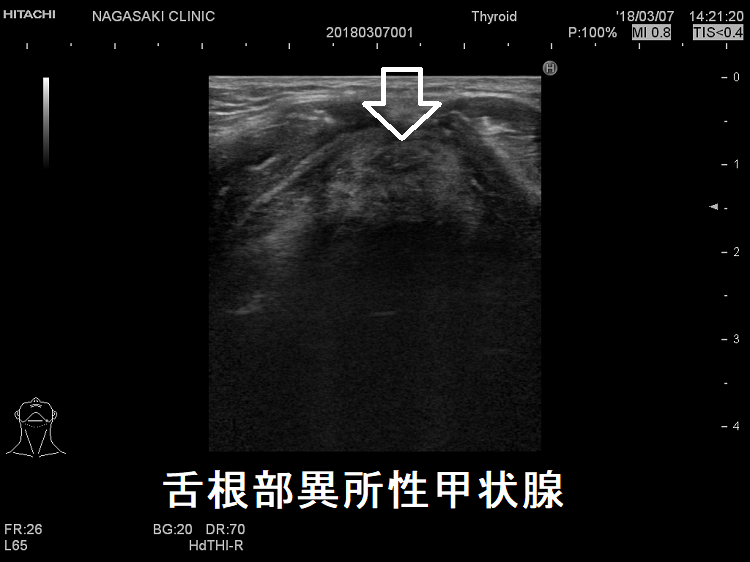

舌根部異所性甲状腺 超音波(エコー)画像

舌根部異所性甲状腺(正位置には無し)